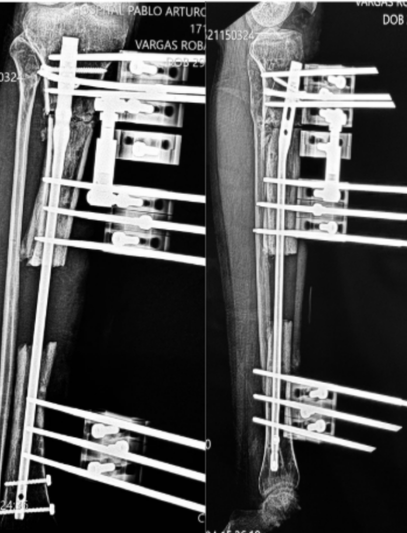

Tras un accidente de tránsito, Yessenia presentó una fractura expuesta con un defecto óseo de 10 cm en su pierna. Había recibido tratamientos previos sin éxito y su movilidad estaba en riesgo.

Con la técnica de osteogénesis por distracción y el uso de un tutor circular Ilizarov, se inició un proceso de regeneración ósea progresiva, acompañado de un seguimiento cercano.

Hoy Yessenia evoluciona favorablemente, conserva movilidad en su rodilla y tobillo, y está recuperando la independencia que pensaba perdida.